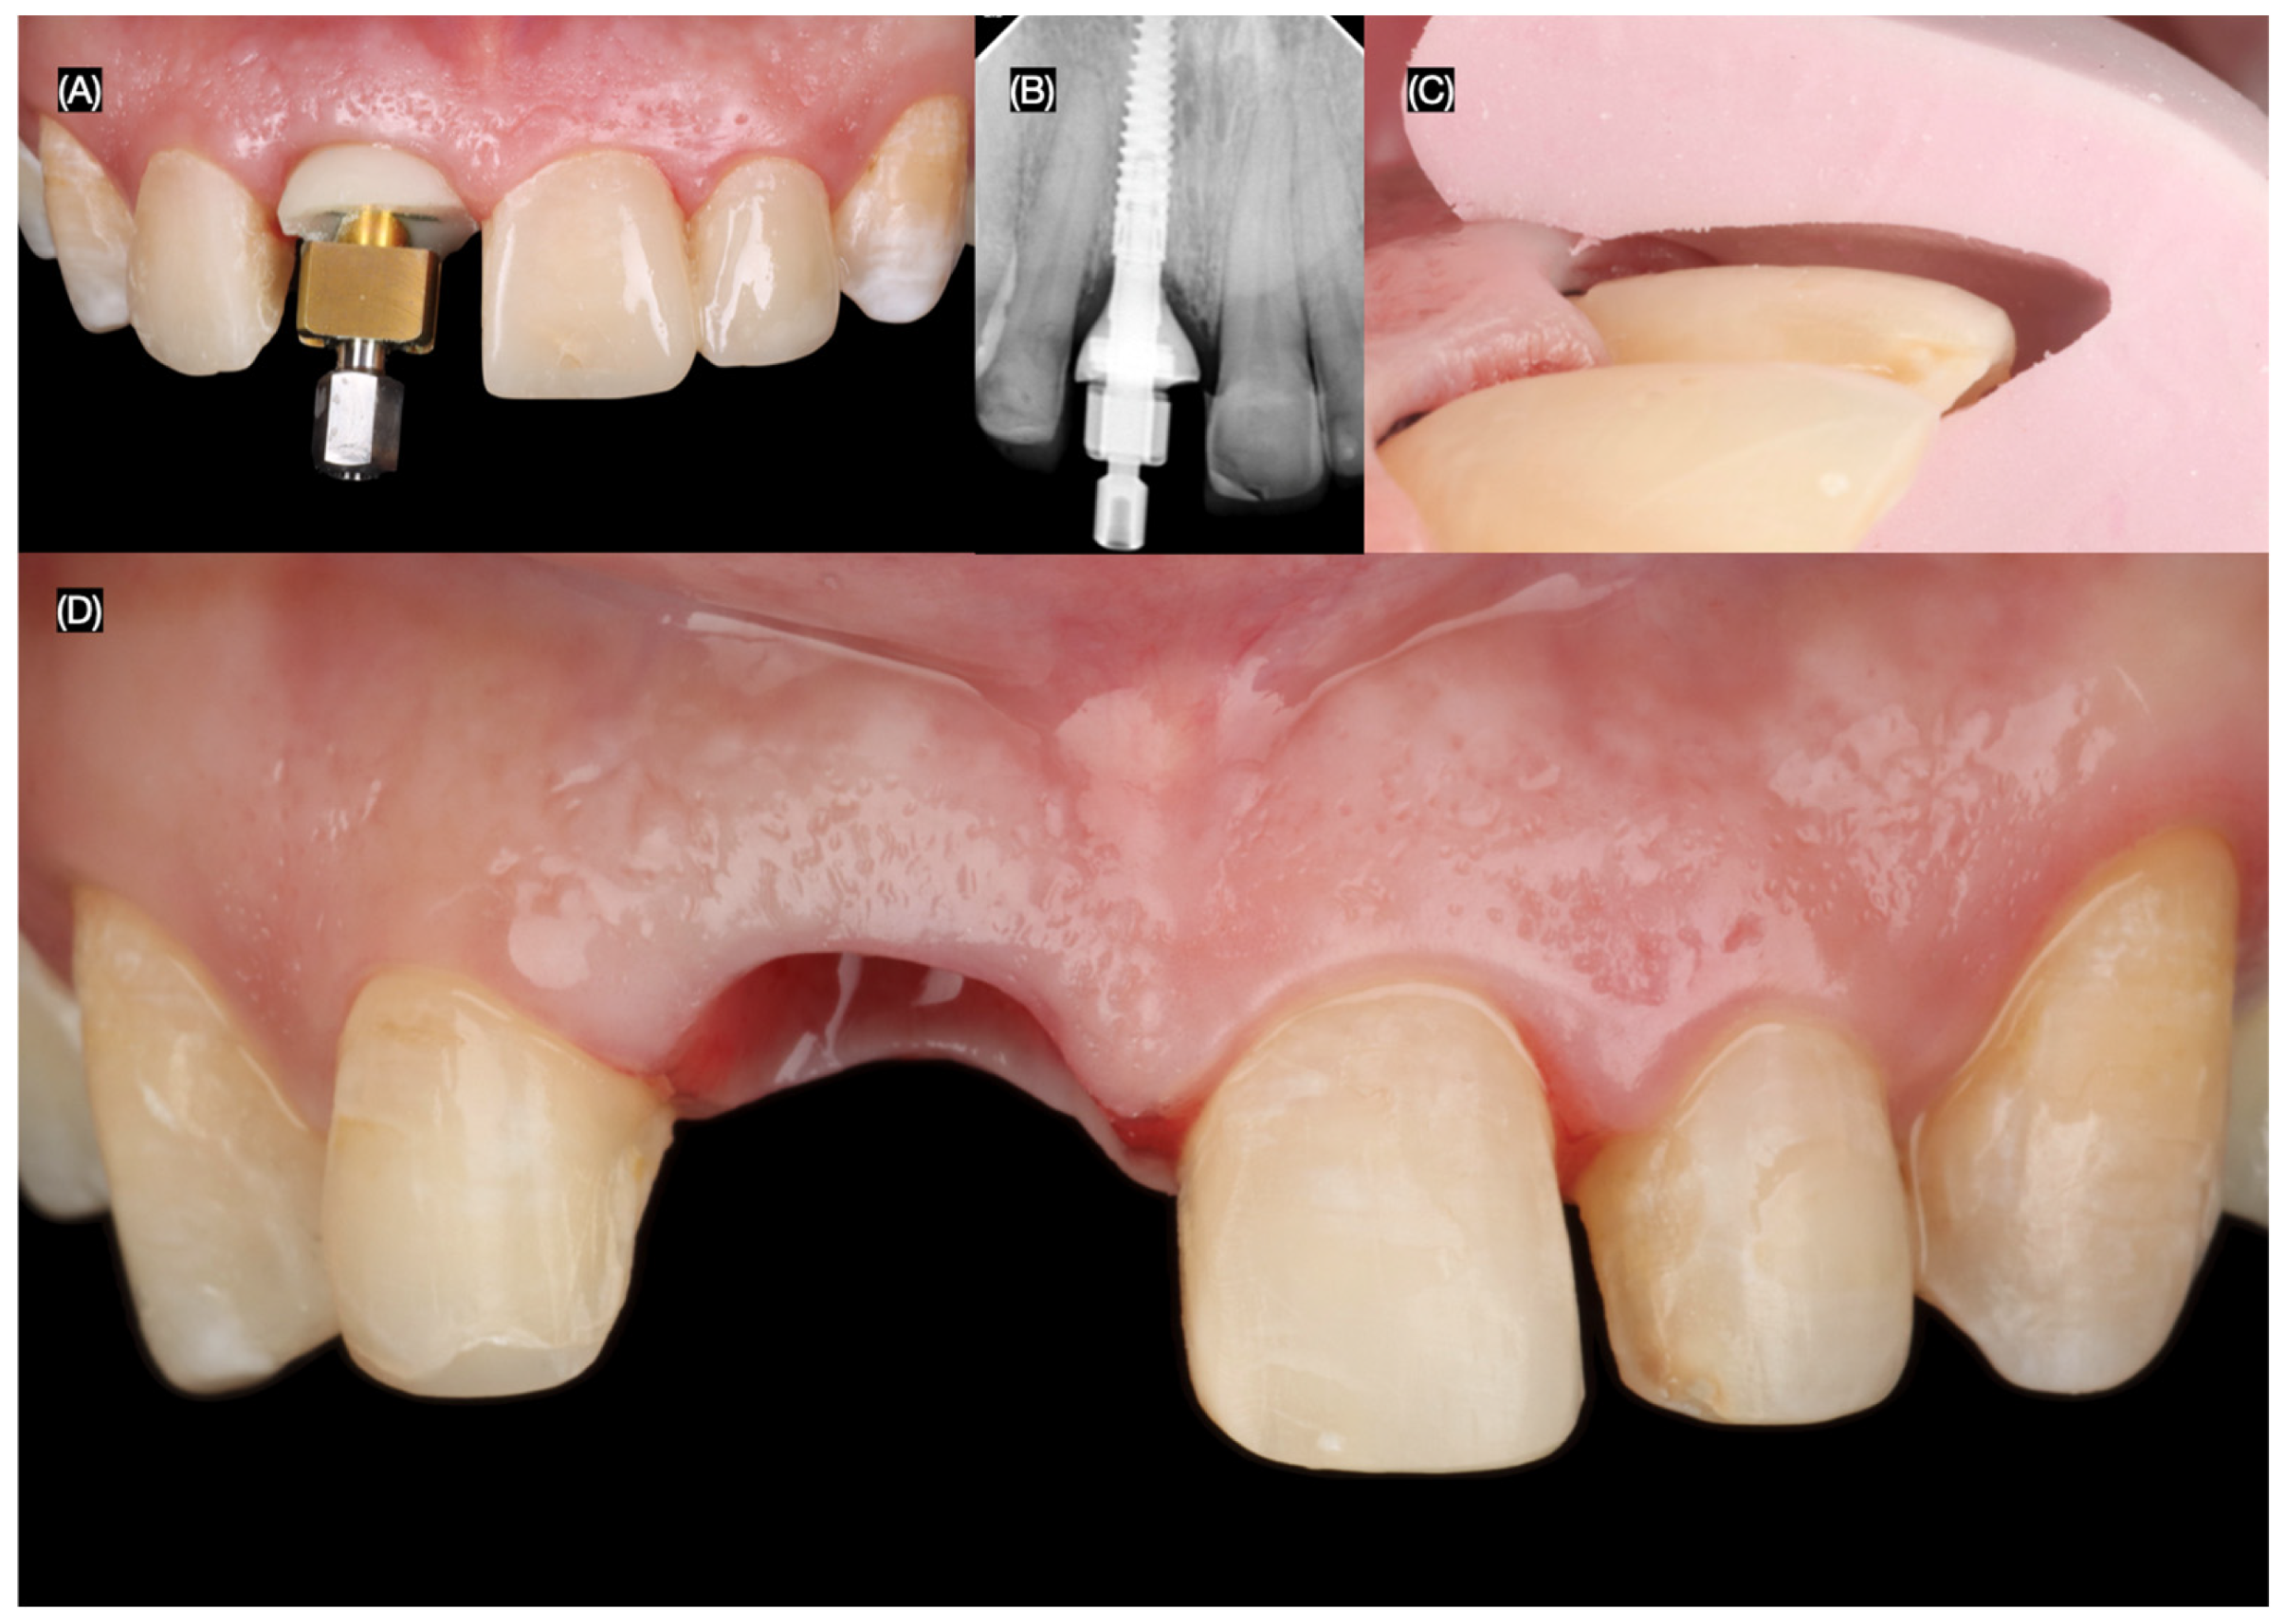

The final screw-retained implant crown was placed, ensuring proper fit, occlusion, and esthetics. A dental dam was then applied to achieve total isolation for the cementation of the veneers, ensuring a clean and controlled environment. The tooth surfaces were first prepared using sandblasting, followed by etching with phosphoric acid. The lithium disilicate veneers were treated with hydrofluoric (Porcelain Etchant, Bisco, Schaumberg, IL, USA) acid for 20 s, thoroughly cleaned in an ultrasonic water bath for 5 min, and coated with a silane (Porcelain Primer, Bisco, Schaumberg, IL, USA) coupling agent for 60 s. Finally, the veneers were bonded using universal adhesive (All Bond Universal, Bisco, Schaumberg, IL, USA) and dual-cure resin cement (Choice 2 Veneer Cement, Bisco, Schaumberg, IL, USA), ensuring a durable and esthetic outcome (Figure 8 and Figure 9).

Figure 8.

Final tooth reparations and impression. (A) Implant impression, (B) radiograph with impression post, (C) tooth preparation with reduction guide, and (D) frontal view of contoured soft tissue and tooth preparations.

Figure 9.

Placement of the final restorations under dental dam isolation. (A) Implant restoration, (B) radiograph of implant restoration, (C) tooth surface treatment with sandblast, and (D) final cementation of restorations.